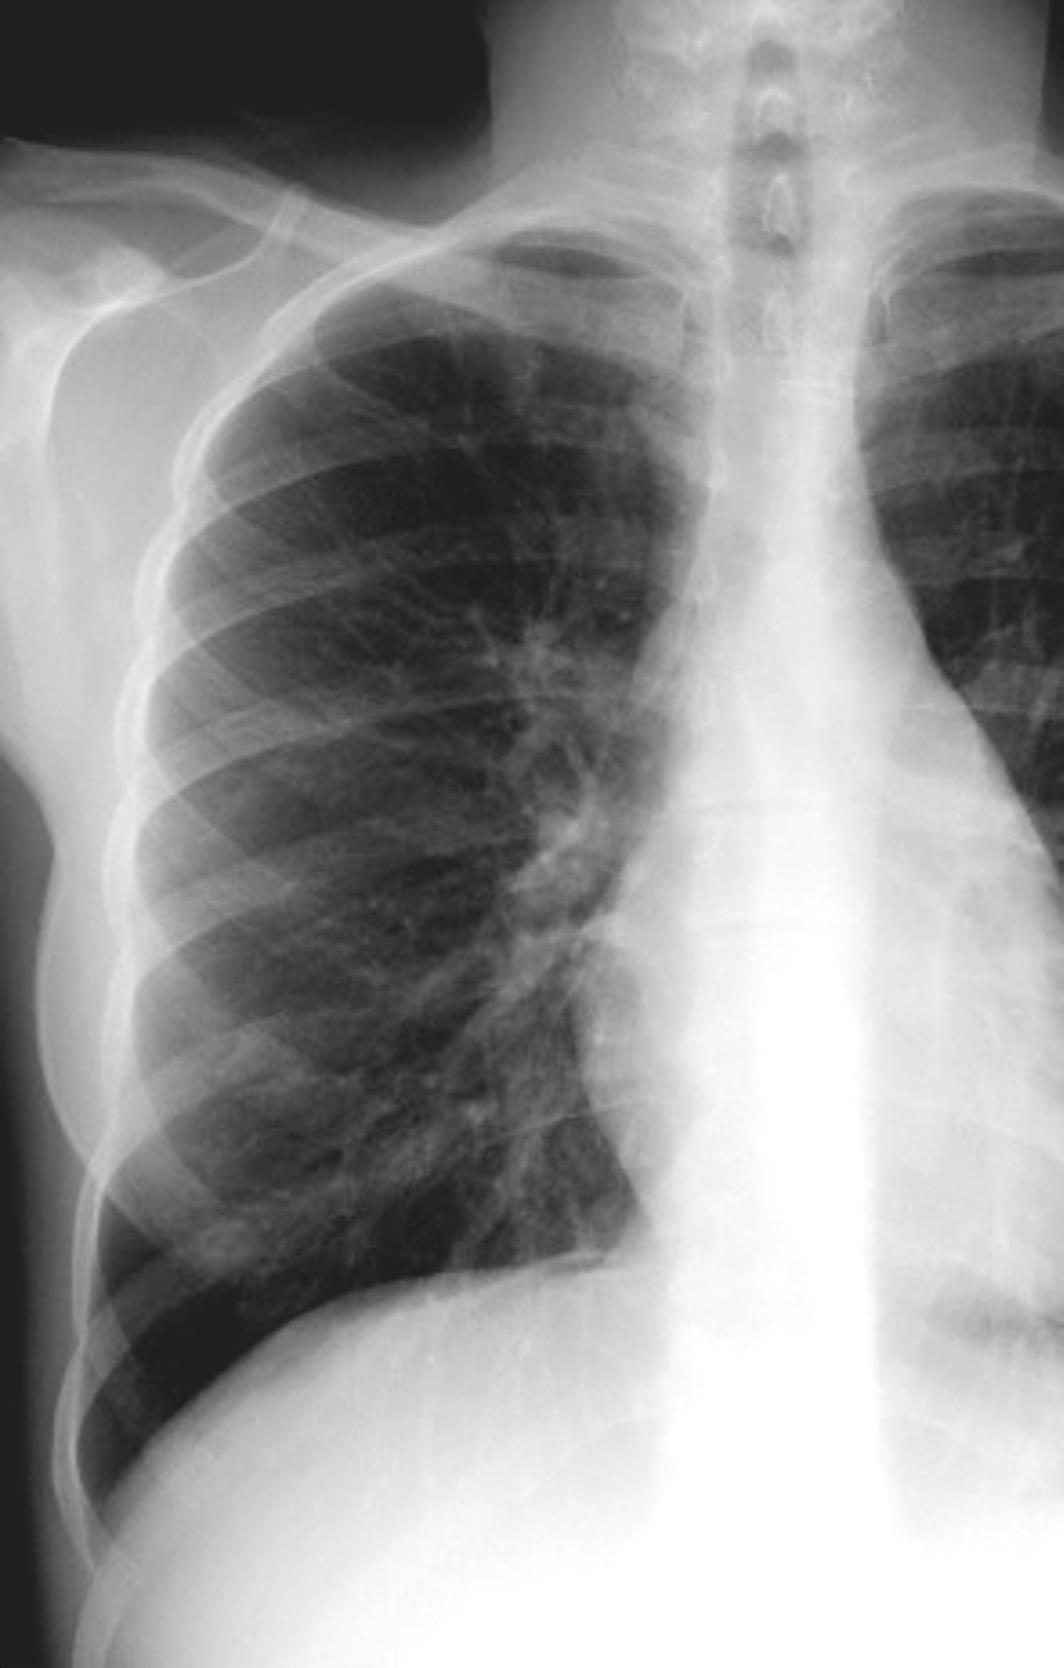

Tromboembolismo pulmonar Diafragma elevado 20%

Consolidación por Infarto pulmonar. (TEP)